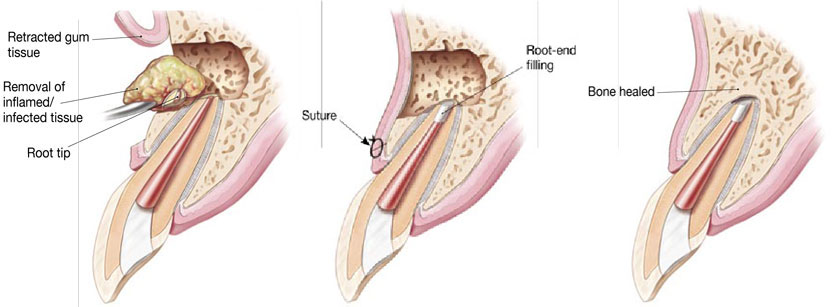

Bone Augmentation

What is it?

Bone augmentation is the changing of the anatomy of the jaw bone by adding a bone graft (artificial bone) in certain areas that are deficient.

Who needs it?

- Insufficient bone for placement of implants.

- The sinus pneumatized, causing insufficient bone height.

- Insufficient facial bone in the esthetic zone.

- To restore facial contour when bone loss occurs due to lesions.